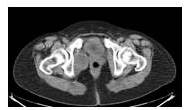

Paciente de 55 años, FUR: 43 años, I gestas, I cesárea, con antecedentes de hipertensión arterial controlada, cáncer de mama derecha, quien es referido por especialista (oncólogo) posterior a realizar CT-PEP control evidenciando LOE pélvico (Figura 1). Es evaluada evidenciándose al examen físico sin alteraciones, se solicita TC abdominopélvica con doble contraste que reporta: masa heterogénea a nivel de músculo isquiorectal derecho, sólido, con áreas de necrosis (Figura 2). Se solicitan paraclínicos: sin anteraciones + citología de cérvix: normal. Se realiza intervención quirúrgica en Clínica la Floresta donde se logra la exéresis de tumoración en su totalidad + toma de muestra de fondo de saco anterior y posterior. El resultado reportó: leiomioma. La paciente actualmente con control ecográfico cada 6 meses sin alteraciones durante su primer año, luego control anual, se encuentra libre de enfermedad a los 6 años de tratamiento.